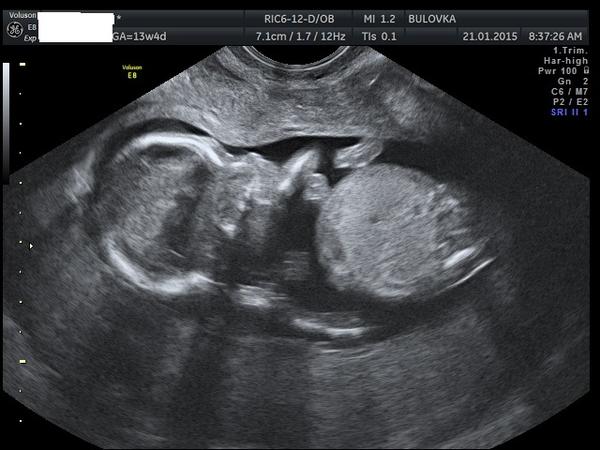

Děvčata, na NT srceeningu mi nechtěli říct pohlaví miminka, že prý to neříkají... vím, že je ještě brzo, ale hodně z Vás to v tomhle období už vědělo....Vidíte tam něco?

@ludul Podle té druhé fotky, vypadá to, jakoby se miminko horní polovinou těla přetáčelo do strany a nožičky ještě zůstaly v původní poloze, vpravo mi připadá, že to vypadá spíš jako ,,kávové zrno'' jak se říká, tedy na holčičku. Ale jo to absolutně amatérský tip 🙂

já zcela amatersky, bez jakýchkoli zkušenosti vidím pindíka, podle té první fotky ... nebo je to stín......tak uvidíme...

Podle první fotky to vypadá na holcicku...

To na co koukáme není ani edno rozkok, ale játra a odstup pupečníku. Takže vydrž. Na. Sice na NT řekli co to bude ale zatím nevěřím, je to oc malinké, takže ještě dva týdny a snad se to 100% dovóme.

Já myslim, že z tehle snímku to nikdo nepozná, protože neni videt mezi nožky🙂 Každopádne podle profilu obličeje bych tipla holčičku 😉